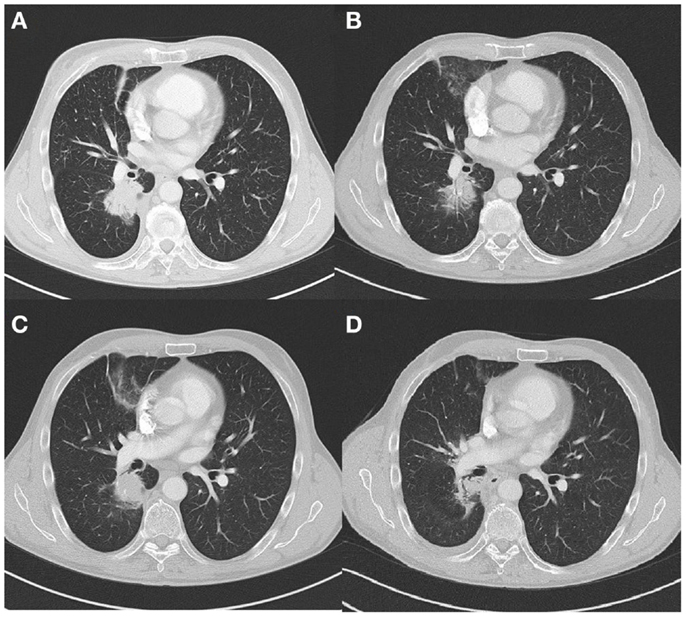

The second case concerns a 66 years old male ex-smoker (6 PY during adolescence). In May 2010, an EGFR mutation (L858R c.2573T > G) positive adenocarcinoma of the right lower lobe of the lung with metastasis in the contra-lateral lung was diagnosed (Figure 2A). In June 2010, afatinib, a irreversible EGFR-HER2-inhibitor, was started in a clinical trial (Gilotrif® in BIBW 2992 trial). The patient experienced partial response (Figure 2B) until July 2012, 26 months after initial diagnosis. At that point, local progression was seen at the site of the primary tumor in the right upper lobe, and no distant metastases (Figure 2C). There was a multidisciplinary consensus to start local hypofractionated radiotherapy (20 Gy × 3 Gy) and stop TKI during this treatment. After completion of the radiotherapy gefitinib was started. A significant decrease of the tumor was seen (Figure 2D). One year later, in June 2013, a new pleural effusion was seen and proven to be metastatic disease. A switch to standard chemotherapy was initiated in October 2013 after pleurodesis. We note stable disease until April 2014. At that point, erlotinib was started because of progressive disease. Four months later, brain metastasis were diagnosed which where treated with whole brain radiotherapy (5 Gy × 4 Gy). Erlotinib was continued afterwards. Until October 2014, we note stable disease.

Figure 2

(A) Tumor lower right lobe on diagnosis (CT scan). (B) Partial response 22 months after start TKI (CT scan). (C) Local progression 26 months after diagnosis (CT scan). (D) Partial response 9 months after local radiotherapy (CT scan).

The third case concerns a 59 years old female never smoker. In January 2009, she was diagnosed with an adenocarcinoma of the lung (left upper lobe) with bone and liver metastasis (Figure 3A). The tumor was EGFR mutation positive, with a deletion found on exon 19. In February, erlotinib was started in a clinical trial (FIELT study) with near complete remission (Figure 3B). 18F-FDG PET-CT showed no distant metastases. After 34 months, the FIELT study was closed. At that point, in December 2011, we made a switch to gefitinib because erlotinib was not yet reimbursed in first-line treatment. In May 2012, 6 months after switch to gefitinib progression of the tumor in the left upper lobe was seen (Figure 3C) and local stereotactic body radiotherapy was given (8 Gy × 7.5 Gy). Gefinitib was stopped during radiotherapy but restarted afterwards. A significant decrease of the tumor was seen (Figure 3D).

Figure 3

(A) Tumor left upper lobe on diagnosis (18F-FDG PET-CT scan). (B) Near complete response 32 months after start TKI (18F-FDG PET-CT scan). (C) Local progression 40 months after diagnosis (18F-FDG PET-CT scan). (D) Partial response 8 months after local radiotherapy (CT scan).

Until October 2014, we note stable disease, 27 months after local therapy.